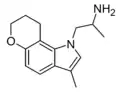

| CP-132,484 | artificial | 1-methyl-4,5-(OCH2CH2CH2) | H | H | 1-(2-aminoethyl)-3-methyl-8,9-dihydropyrano(3,2-e)indole | 143508-76-3 |

| 4,5-DHP-DMT | artificial | 4,5-(OCH2CH2CH2) | CH3 | CH3 | 1-(2-dimethylaminoethyl)-8,9-dihydropyrano[3,2-e]indole | 135360-97-3 |